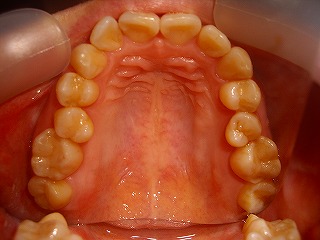

治療後の上顎                        治療後の下顎